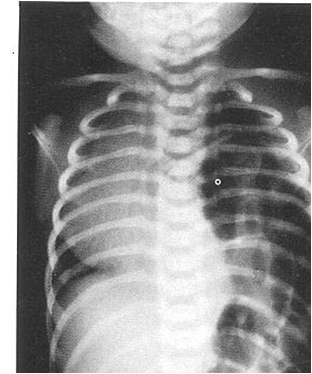

产后诊断Diagnosis after birth

胸腹部正侧位摄片:

◇ 可见患侧胸腔内有典型的充气胃和肠曲,并向腹部延续现象。

◇ 病变侧看不到正常膈肌 形态。

◇ 腹部气体影减少。